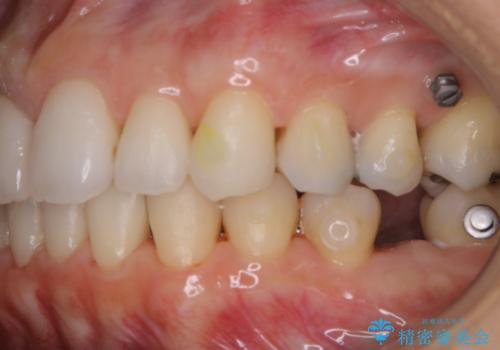

- インビザラインでのマウスピース矯正中にステインや着色を取りたいとのことでした。

PMTC60分コースを行いました。

PMTC(保険外治療)は、毎日の歯磨きで落としきれない汚れや、コーヒ、紅茶・タバコのヤニなどの着色も除去します。目には見えない歯と歯の間・歯肉の境目・インビザライン中はアタッチメント周囲などに残っているプラーク(歯垢)もしっかり取り除きます。PMTCでは専門的な機械や材料を使用して、徹底的に汚れを除去するため、虫歯・歯周病・口臭予防などにつながります。